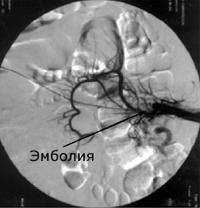

Наиболее точным методом исследования является ангиография мезентериальных сосудов. Данное исследование рекомендуют проводить в двух проекциях – прямой и боковой. Такая методика позволяет вычислить точную локализацию патологического процесса, выявить пораженные ветви висцеральных сосудов, определить тактику и объем оперативного вмешательства. Помогает в диагностике и определении лечебной тактики и консультация врача-эндоскописта.

При обзорной рентгенографии брюшной полости определяется пневматизация кишечника, наличие горизонтальных уровней жидкости в брюшной полости. Специфическим методом диагностики острой окклюзии мезентериальных сосудов является селективная мезентерикография, которая уже на ранней стадии заболевания может выявить отсутствие кровотока в стволе и ветвях брыжеечной артерии. При наличии технической возможности выполняется магнитно-резонансная ангиография мезентериальных сосудов.